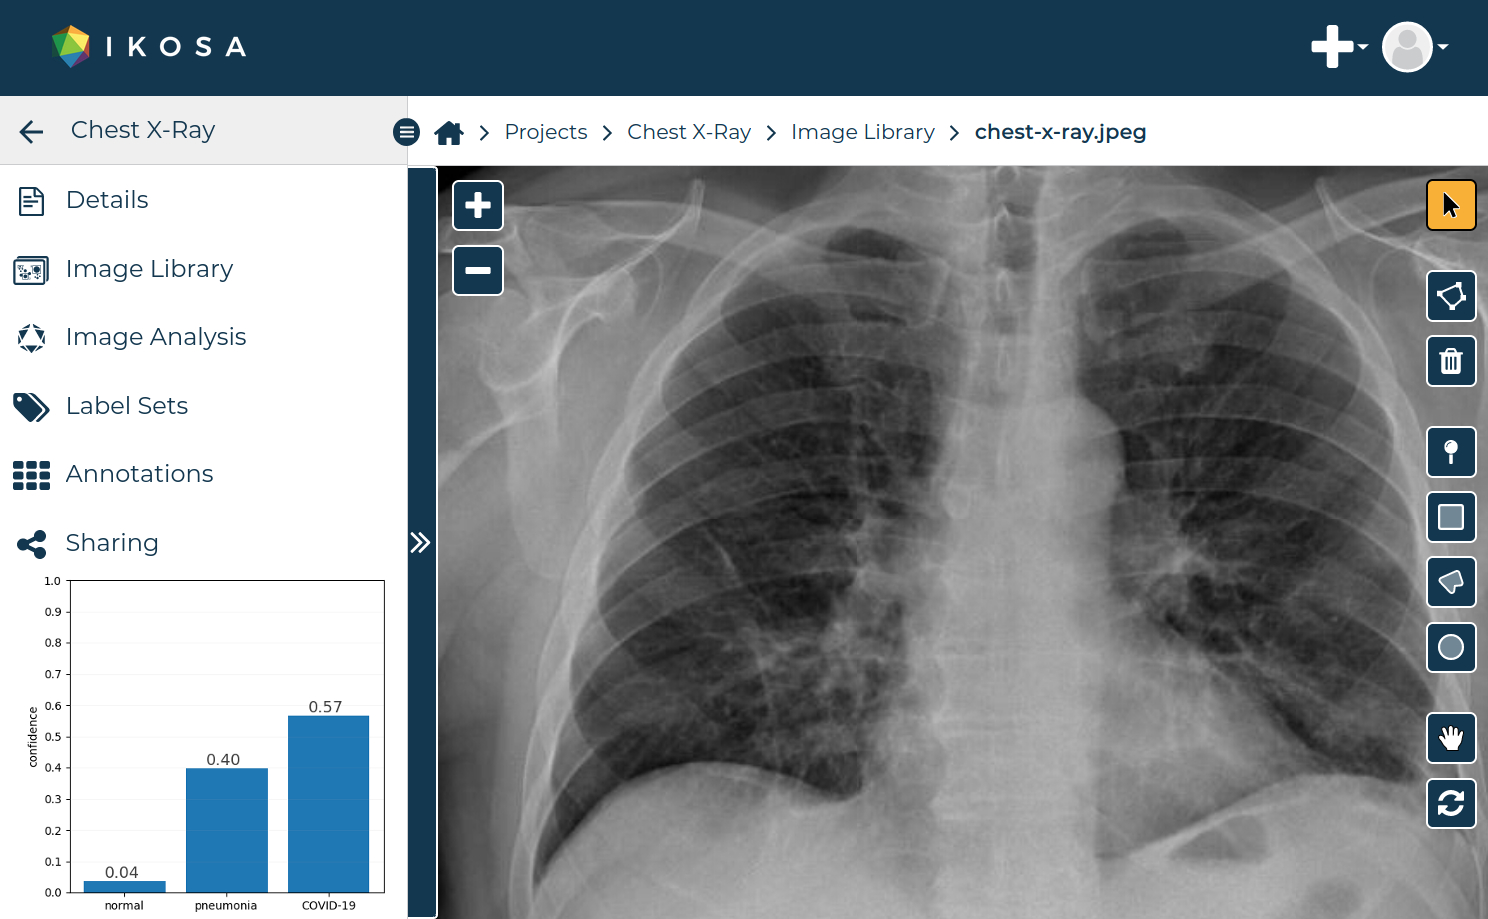

Mit dem Ziel den Algorithmus allen Interessierten möglichst einfach zugänglich zu machen, stellt ihn KML Vision ab sofort als Bildanalyse-Anwendung auf ihrer Onlineplattform IKOSA® kostenfrei zur Verfügung. Durch den Zugriff auf die Onlineplattform und die selbsterklärende Benutzeroberfläche kann jeder User die COVID-19-Applikationen und andere Anwendungen mit nur wenigen Klicks und ohne Programmierkenntnisse testen. Innerhalb von Sekunden wird ein Röntgenbild als normal, eine Lungenentzündung oder eine COVID-19 Erkrankung erkannt. Hätte man Röntgenbilder von jedem Menschen der Erde, könnte man durch den Einsatz dieser KI-Anwendung die ganze Weltbevölkerung in wenigen Tagen testen. Die Möglichkeit der einfachen und raschen Integration neuer Anwendungen ist dabei ein entscheidender Vorteil der skalierbaren Plattform, die gleichzeitigen Zugriff für eine Vielzahl von Nutzern erlaubt. Damit hat es KML Vision geschafft, in kürzester Zeit nach der Veröffentlichung, dieses erfolgsversprechende Werkzeug der weltweiten Forschungsgemeinschaft zur Begutachtung anzubieten.